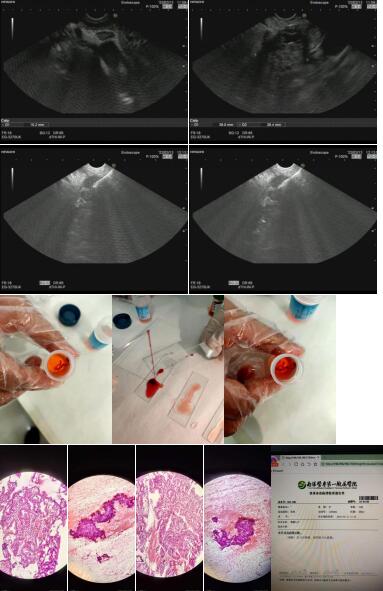

1.超声内镜(EUS)扫查癌肿起源和浸润深度,提供术前T/N分期诊断,我们配备有PENTAX的大超和英美达的小超(含12MHz和12MHz两个探头),大小超相互补充,每月做40-50例左右;

5.超声引导下细针穿刺(EUS-FNA)诊断胆胰及纵膈占位性病变,已穿刺5例,均获取阳性结果,无一例发生术后并发症。

病例二:胰头占位内镜超声引导下细针穿刺抽吸活检,穿刺结果:胰腺乳头状肿瘤,倾向高分化腺癌。